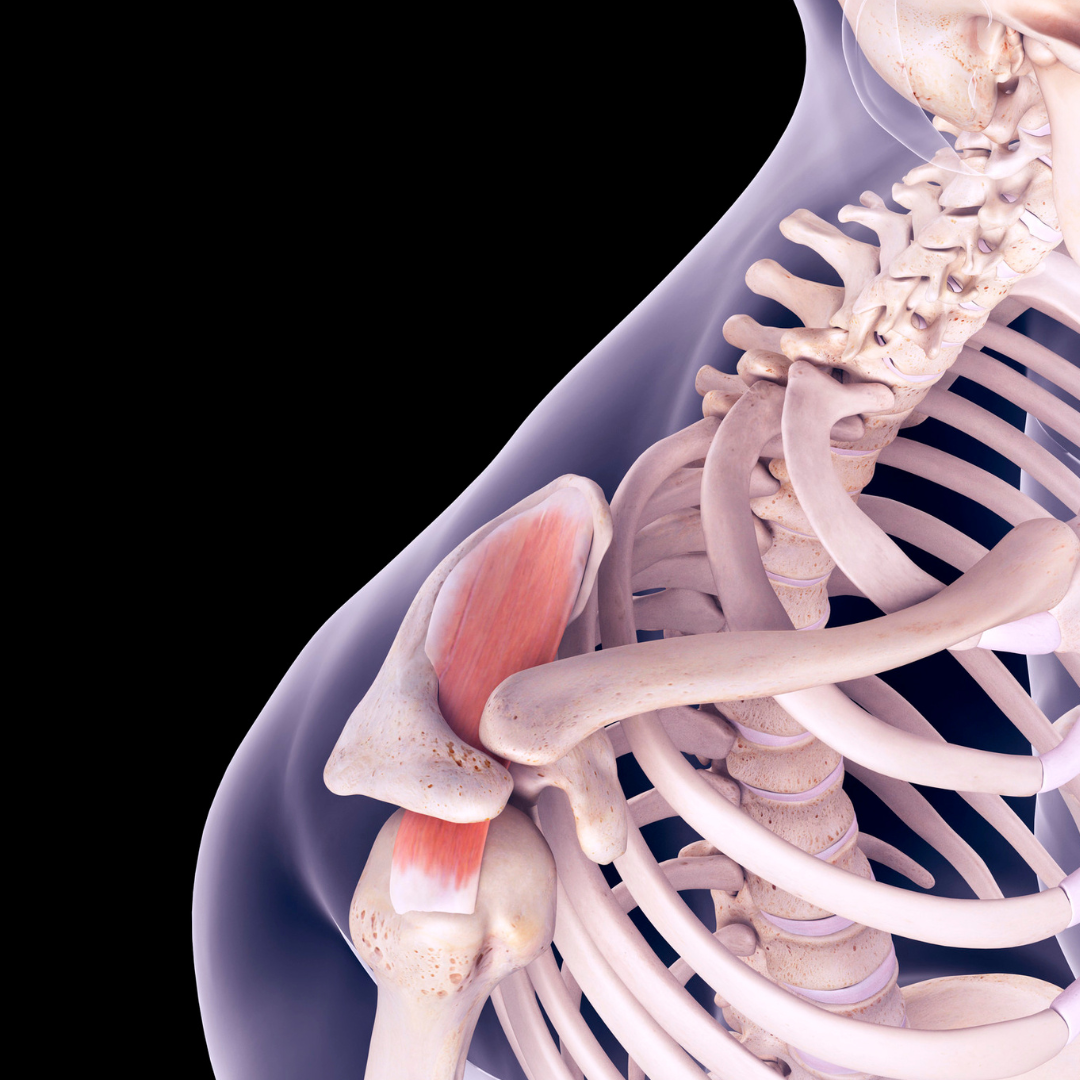

Rama

Rama je eden najbolj gibljivih, a hkrati nestabilnih sklepov v telesu, saj omogoča širok obseg gibanja v vseh smereh. Zaradi kompleksne anatomske zgradbe, ki vključuje kosti, mišice, kite, vezi in hrustančni labrum, je rama izpostavljena številnim poškodbam, kot so tendinopatije, natrganja rotatorne manšete, utesnitveni sindromi, izpahi in labralne lezije.

Poškodbe ramenskega sklepa so pogosto posledica preobremenitev, ponavljajočih se gibov ali akutnih travm, zato je ključna ustrezna preventiva, rehabilitacija in krepitev stabilizacijskih struktur.

Poškodbe mišice supraspinatus

Kaj morate vedeti?

Supraspinatus je ena od mišic rotatorne manšete, ki sodeluje pri dvigovanju roke in stabilizaciji ramenskega sklepa. Poškodbe supraspinatusa pogosto nastanejo zaradi ponavljajočih se gibov, preobremenitev ali degenerativnih sprememb, ki vodijo do vnetja ali rupture tetive.